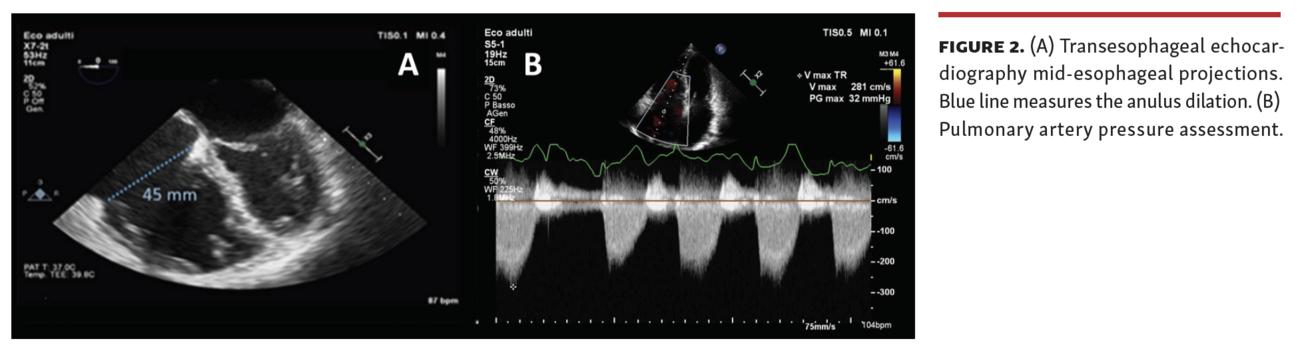

The efficacy of transcatheter edge-to-edge tricuspid valve repair (TTVR) has been recently demonstrated not only for the reduction of tricuspid regurgitation (TR) but also in terms of right ventricular remodeling. We report the case of a 78-year-old female patient with a history of atrial fibrillation and severe isolated TR in New York Heart Association functional classification III despite optimal medical therapy. The preprocedural transesophageal echocardiography (TEE) showed severe TR associated with Ebstein’s-like valve displacement, and dilation of the right atrium and ventricle with “atrialized” portion. The tricuspid annulus plane systolic excursion was preserved (20 mm) with acceptable systolic pulmonary artery pressure (PAP) of 30 mmHg (Figure 1 and Figure 2; Video Series).